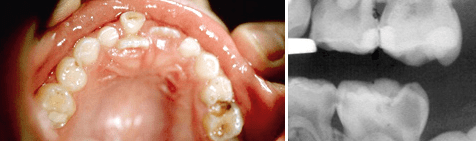

Aus den geschilderten Besonderheiten der Milchzähne ergibt sich zunächst die Forderung nach einer sorgfältigen Diagnostik und Behandlungsplanung. Grundsätzlich sollte vor Beginn der Behandlung eines Milchzahns klar sein, welchen Stellenwert der Zahn in der Gebissentwicklung einnimmt, wie die Pulpa des betreffenden Zahnes beschaffen ist und welche Therapiealternativen für welche Diagnosen infrage kommen. Die Anamnese kann mit Angaben zur Schmerzlokalisation und -dauer wertvolle Hinweise liefern. Bei der klinischen Untersuchung zeigen Rötungen der Gingiva, Schwellungen oder Fisteln in der Umgebung kariöser Milchzähne, dass die Entzündung bereits bis in den Kieferknochen vorgedrungen und der betreffende Zahn damit avital ist. Wenn solche klaren klinischen Zeichen fehlen, ist das Röntgenbild die wichtigste Informationsquelle um Fehldiagnosen zu vermeiden (Abb. 2). Wesentliche Informationen aus dem Röntgenbild sind u.a.: Ausmaß der Karies, Stand der physiologischen Wurzelresorption, pathologische (entzündliche) Resorptionen der Zahnwurzeln, interradikuläre Knochenresorptionen, Veränderungen der Pulpa (z.B. Dentikel), die Anatomie der Zahnwurzeln bzw. die Lokalisation und der Entwicklungsstand des nachfolgenden permanenten Zahnes.

Abb. 2 Bissflügel-Röntgenaufnahme.